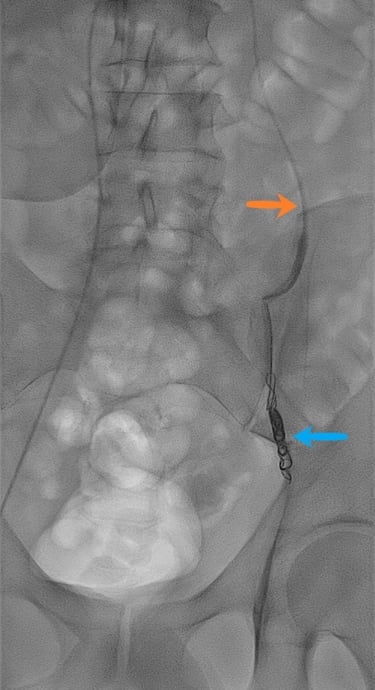

Exemple d'images d'embolisation réalisée dans le service.

Deuxième image, à droite : phase de traitement avec cathéter (flèche orange) en place dans la veine spermatique, avec mise en place de coils d'embolisation (flèche bleue), permettant l'occlusion de la veine.